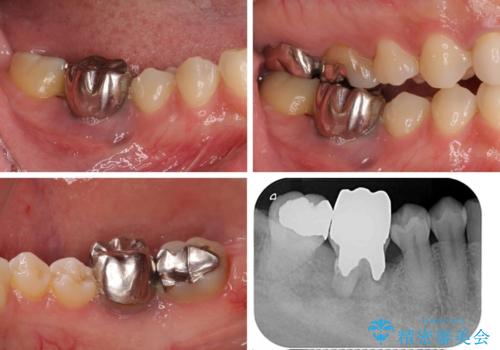

- 右下の奥歯が痛く、全体的に咬み合わせがおかしい気がするとのことで来院された患者様です。

診察したところ、上顎前歯に過剰歯があることで上顎歯列が大きくなり、上下の歯が奥歯の一部でしか咬み合っていない状態でした。

そのため右下の奥歯に強い負担が生じていて、むし歯が大きかったこともあり、抜歯が必要な状態でした。

咬み合わせ改善のため、前歯の過剰歯を抜去し、ワイヤー矯正にて歯列と咬み合わせることとしました。

左上の奥歯のブリッジや前歯のセラミッククラウンはいったん除去し、矯正治療後に補綴治療を行うこととしました。

また、右下の抜歯が必要な奥歯は、矯正治療の途中でインプラントを埋入し、矯正治療後に上顎と合わせて補綴治療を行うこととしました。